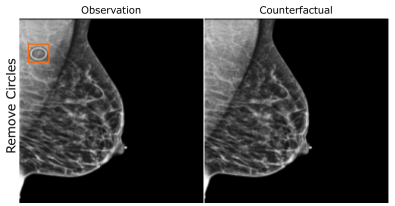

EMBED

Using prior insights, we apply our mechanisms to a real-world artefact removal task on the EMory BrEast imaging Dataset (EMBED) (Jeong et al., 2022). Schueppert et al. (2024) observe that triangular and circular skin markers are spuriously associated with breast cancer in classifiers due to shortcut learning (Geirhos et al., 2020), and manually labelled 22,012 affected mammograms. Using this dataset, we train a significantly scaled-up, amortised, anti-causally guided semantic mechanism () to remove skin markers. We model triangular markers (), circular markers (), breast density (), and cancer () as independent parents of the mammogram , and remove artefacts by intervening on and while holding and fixed. Figure 6 shows that our mechanisms effectively remove artefacts and can disentangle representations for triangles and circles. We successfully remove of triangles and of circles in our test set - a noteworthy result given the dataset’s small size and the scarcity of labelled skin markers (Appendix I).